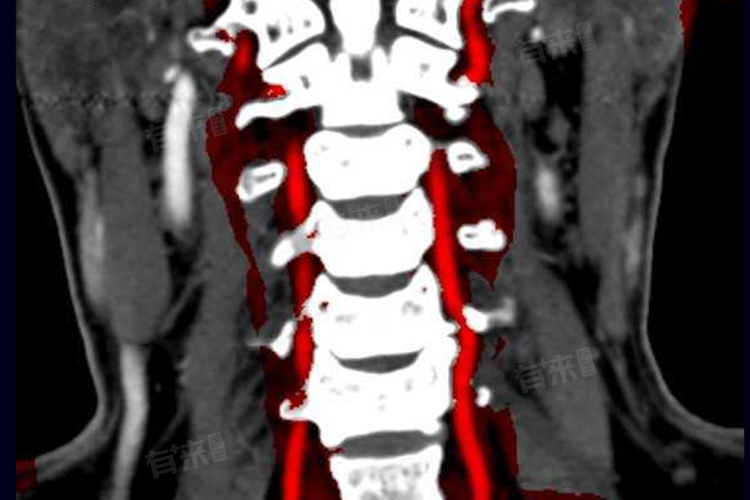

椎动脉狭窄的症状包括眩晕、头痛、视力障碍等,椎动脉狭窄指的是椎动脉管腔因各种原因出现变窄的情况,椎动脉是人体重要的供血血管,左右各一,从锁骨下动脉发出,向上穿行颈椎横突孔,最后在脑桥下缘汇合成一条基底动脉,为大脑后循环,包括脑干、小脑、枕叶等部位提供血液供应。